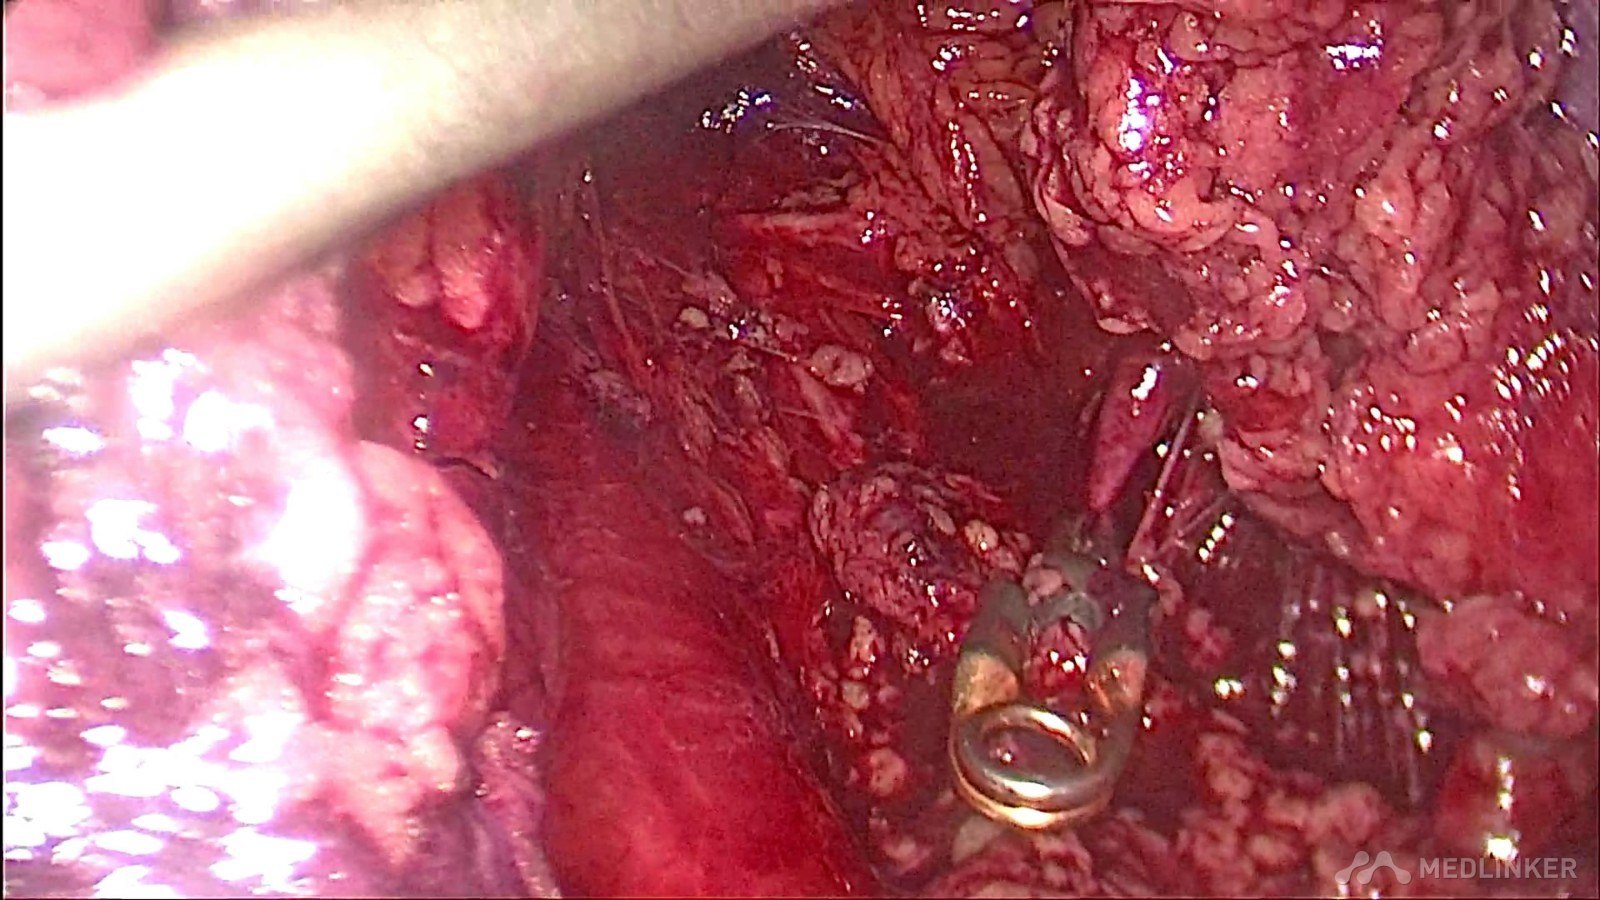

充分游离右肾动脉及分支,阻断血流,防止大出血的发生,降低输血几率

完整切除分叶状肿瘤

术中快速病理提示为右肾错构瘤